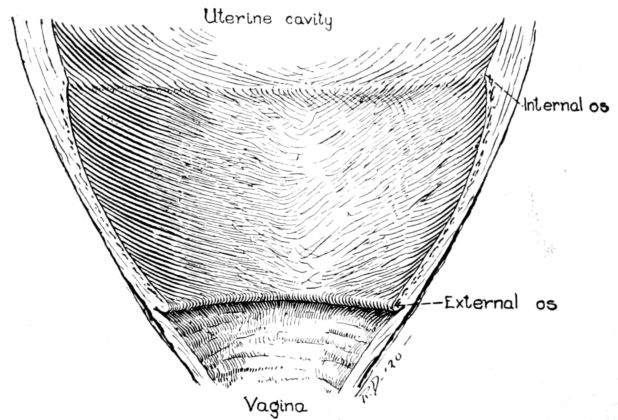

| xxi63, 64, 65, 66. | Diagrams showing stages of dilatation and obliteration of cervix | 234 |

The uterus as a whole is comprised of three parts: the fundus, that firm, rounded, head-like part above; the body, or middle portion, and the cervix, or neck, below. It is in the body and cervix that we find the long, narrow uterine cavity, divided by a constriction into two parts. The cavity of the body is little more than a vertical slit, being so flattened from before backward 33that the anterior and posterior surfaces are nearly if not quite in apposition. It is somewhat triangular in shape with an opening at each angle. (Fig. 11.) The lower of these openings leads into the cavity of the cervix through a constriction termed the internal os, while at the cornua, or two upper angles, are the openings into the Fallopian tubes.

The cavity of the cervix is spindle-shaped, being expanded between its two constricted openings, the internal os above and the external os below, which opens into the vagina. The external os in the virgin is a small round hole but has a ragged outline in women who have borne children.